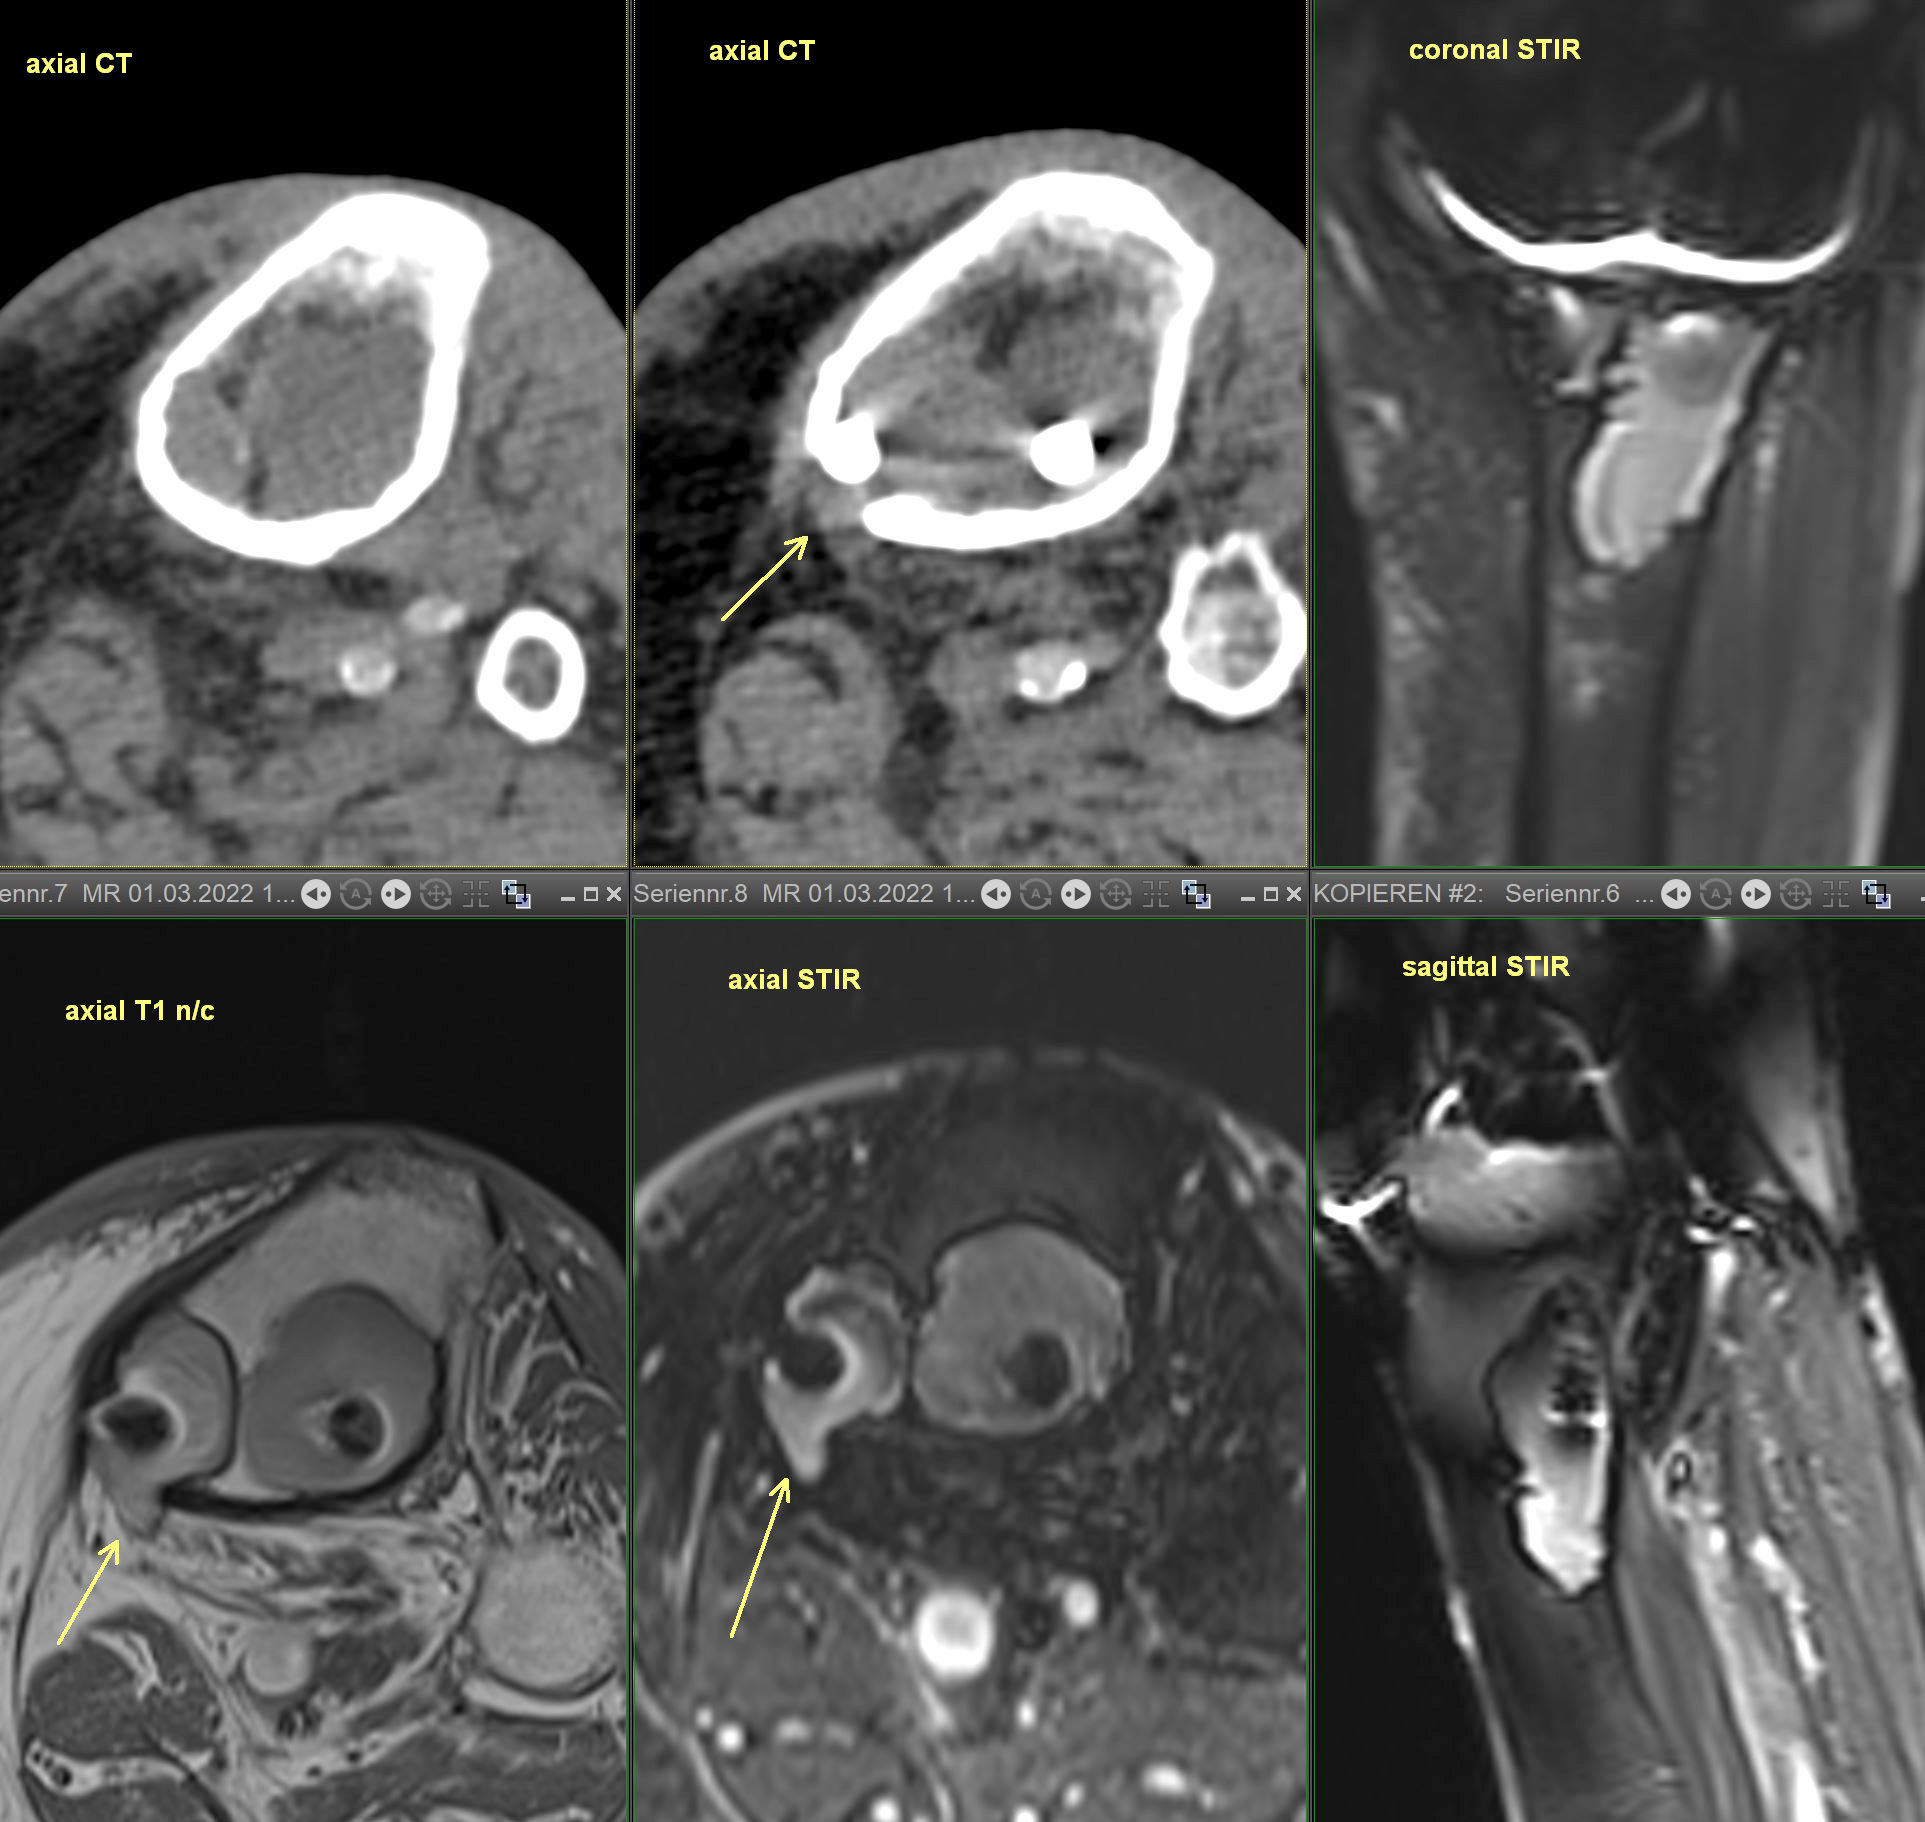

x-ray - Progressive osteopenia and lucency around tip of tibial screw. CT - lytic bone changes at the tibial prosthesis with a medial cortical defect. MR - cystic bone lesions at the tibial arthroplasty component extend out of the bone through a small defect. No surrounding marrow or soft tissue edema at this level.

Presumed chronic material-related osteolysis